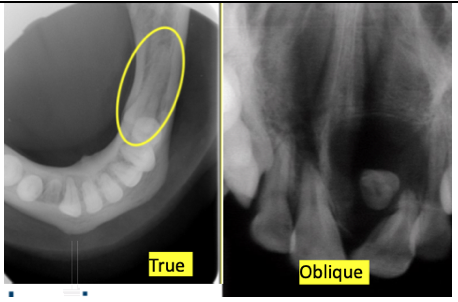

Name this type of radiograph?

Occlusal. There are 2 types: